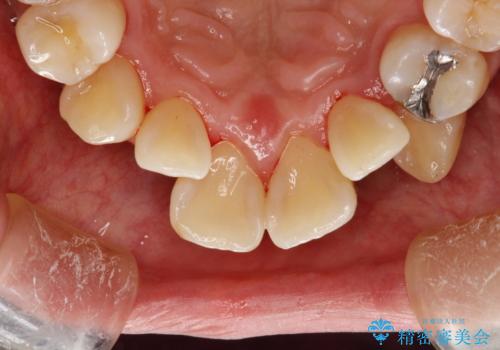

プラーク(細菌の塊)や歯石がたまると歯の表面はザラつきいてきます。そのザラつきは歯周病や虫歯菌の棲家となります。そのまま放置すると、歯肉が腫れてきたり、歯肉から出血したり、口臭が強くでたりします。とくに歯肉の境目は、歯磨きで汚れを除去することが難しく、プラーク(細菌の塊)や歯石が溜まりやすい場所です。

歯並が、がたついている場合はなおさら汚れが溜まりやすいです。矯正治療前や矯正中、定期的にPMTCをすることで、矯正治療中の歯肉トラブルを防ぐことにつながります。

- これから矯正治療を始めるため、今の状態でも歯をきれいにしておきたいとのことでした。PMTC60分コースを行いました。